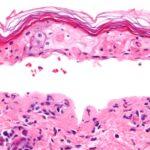

Mucoepidermoid carcinoma is a malignant tumor made up of squamous and mucin-producing cells.

Mucoepidermoid carcinoma is the most common malignant tumor of the salivary gland.

Mucoepidermoid carcinoma often occurs in the parotid.

The facial nerve is frequently compromised by mucoepidermoid carcinoma.